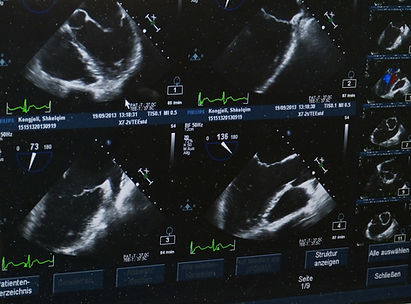

Ultrasonography

VIP offers full ultrasonography services for evaluation of abdominal organs, pregnancy evaluations, pregnancy monitoring, as well as performing cardiac studies that can be sent for a detailed analysis by a board-certified cardiologist.

VIP uses the extremely efficient Butterfly brand ultrasound system that provides great detail with excellent portability.  This system allows us to use our large screen diagnostic monitors to perform the study with you, in real time.